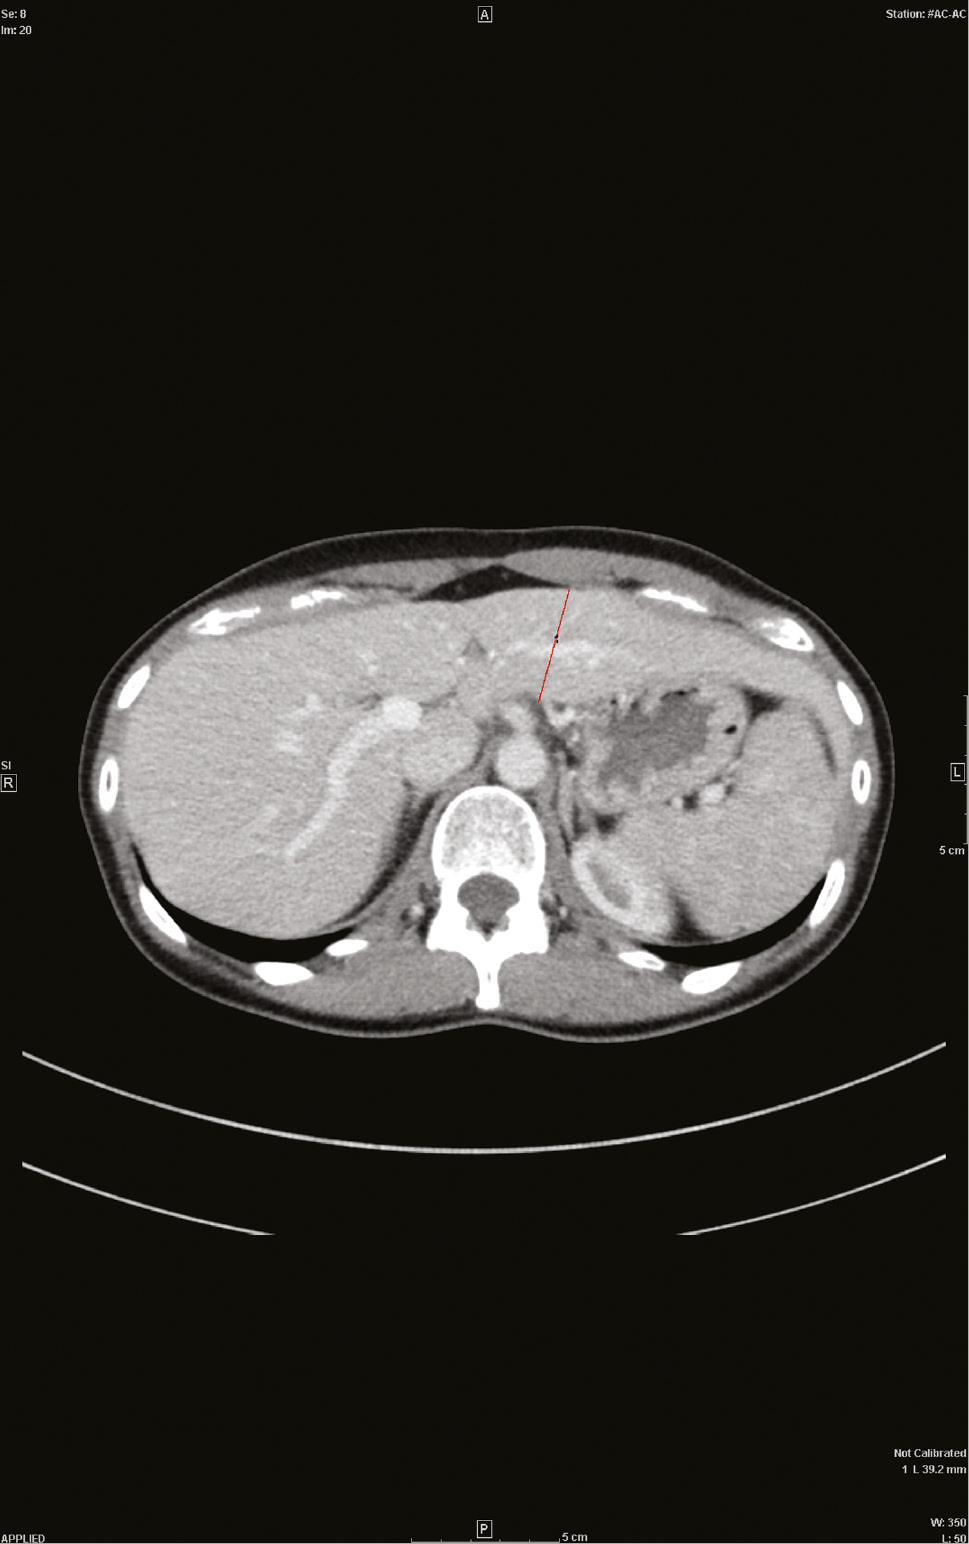

In cases, the preoperative CT scans of the donor were evaluated and the diameter of segment II/III was assessed in all three dimensions: ventro-dorsal (thickness), cranio-caudal (length), and transversal (width) (Figure 1). The total liver volume was calculated after boundaries of the hepatic lobe were drawn manually on consecutive 5-mm-thick axial portal-venous phase CT images (no gap). Volumes were calculated by multiplying the slice thickness with the sum of all traced areas of the respective hepatic lobe. Manual measurement was favoured over automatic measurements, as automatic programs identify the left hepatic vein as the boundary whereas transplant surgeons choose their resection plane slightly moving into segment IV, so that automatic measurements would deliver too small values for the estimated graft volume.

Figure 1: CT of the liver.Axial portal-venous phase CT image with the ventro-dorsal diameter of a female donor liver.

Figure 1:

CT of the liver.

Axial portal-venous phase CT image with the ventro-dorsal diameter of a female donor liver.